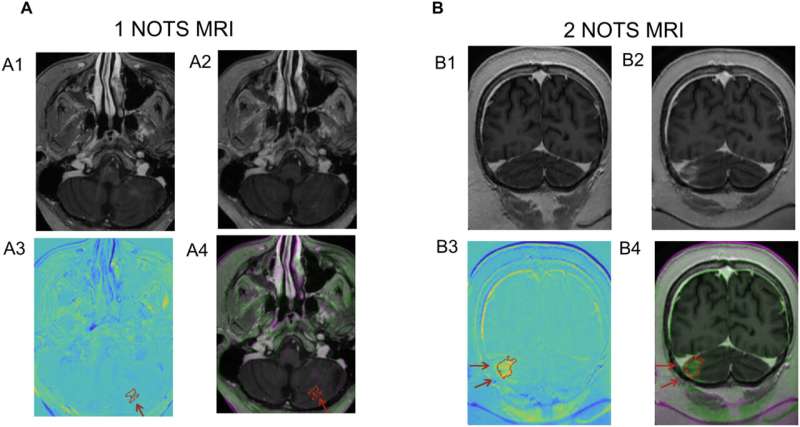

The focused ultrasound technique, developed by Columbia engineers, was tested in combination with chemotherapy in three children with diffuse midline glioma, a rare and aggressive brain cancer that is universally fatal. The study is published in the journal Science Translational Medicine.

The study found that focused ultrasound successfully opened the blood–brain barrier in all three patients, allowing the chemotherapy drug to reach the tumors and leading to some improvement in patient mobility. (All three patients eventually died from their disease or complications of COVID.)